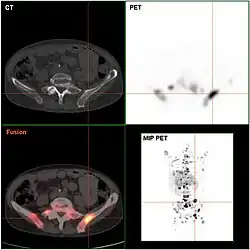

Endokrin aktive Tumoren (funktionelle NET) können frühzeitig aus den klinischen Symptomen vermutet und durch gezielte Laboruntersuchungen (etwa bei histologisch gesicherten NEN die Bestimmung von Chromogranin A im Serum[6]) des Blutes nachgewiesen werden. Inaktive Tumoren (nicht-funktionelle NET) werden oft erst spät durch ihre Größe oder infolge von Metastasen auffällig. Bildgebende Verfahren können die Lage des Tumors aufdecken: Sonographie, Computer- und Kernspintomographie, oder auch spezielle Szintigraphien wie die Somatostatin-Rezeptor-Szintigrafie mit Indium-111 oder MIBG-Szintigrafie. Neu entwickelt ist die Positronenemissionstomographie mit radioaktiv markiertem DOPA bzw. Edotreotid (DOTATOC), deren Sensitivität und Spezifität der klassischen Szintigraphie mit Somatostatinanaloga um bis zu 30 % überlegen ist.[7][8]